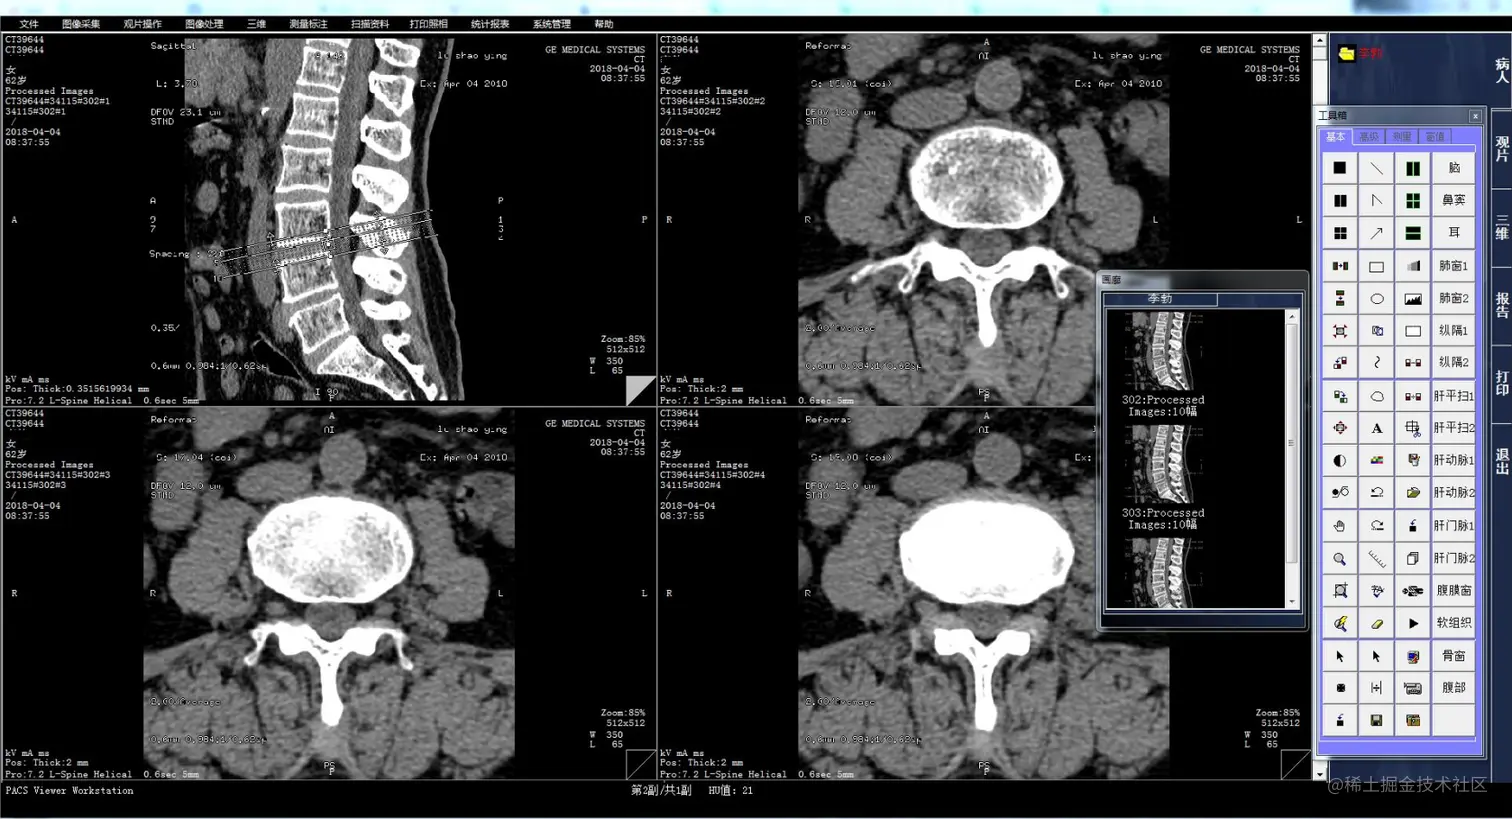

三、CT检查

CT检查(Computed Tomography,计算机断层扫描)是一种利用X射线进行断层扫描的医学影像诊断方法。它通过在不同角度发射X射线,利用计算机重建人体的断层图像,以检测病变和损伤。

CT检查通常采用横断面扫描,可以在不同层面上进行扫描,以获取更精确的图像。与传统的X射线相比,CT检查能够提供更高质量的图像,并能够更准确地诊断病变和损伤。

三维表面重建.png CT检查广泛应用于临床诊断和治疗中,如头部、胸部、腹部等。在头部检查中,CT检查能够检测脑出血、脑梗塞、脑肿瘤等病变;在胸部检查中,CT检查能够检测肺结节、肺栓塞、肺癌等病变;在腹部检查中,CT检查能够检测肝、胆、胰、脾等器官的病变。

CT检查是一种无创、安全、准确的诊断方法,对于早期发现和诊断病变,以及指导治疗和手术具有重要意义。同时,CT检查也能够提供更多的信息,如病变的大小、形态、位置、密度等,以帮助医生更准确地诊断和治疗疾病。